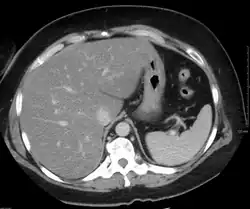

Жировой гепатоз при компьютерной томографии с внутривенным контрастным усилением. Отмечается диффузная гиподенсивность паренхимы печени.

При компьютерной томографии выявляется в разной степени выраженное диффузное снижение денситометрических показателей паренхимы печени (ниже 55 HU, иногда вплоть до отрицательных значений, соответствующих плотности жира), как правило отмечается увеличение размеров органа. Возможно выявление ограниченных участков жировой инфильтрации, окружённых неизменённой тканью печени. Чаще локальная жировая инфильтрация наблюдается в сегменте S4 печени, имеет довольно ровные, прямые контуры, ход сосудов в инфильтрированной жиром ткани не изменён, масс-эффект (объёмное воздействие на окружающие структуры) отсутствует.